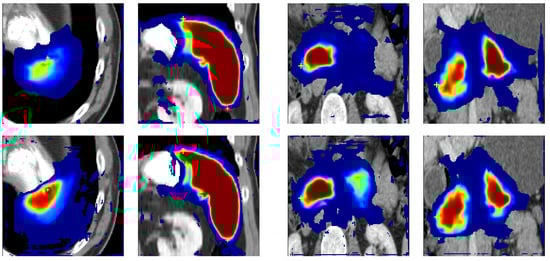

3.4. Analysis of Point Loss

3.5. Effect of Extreme Point Noise during Inference